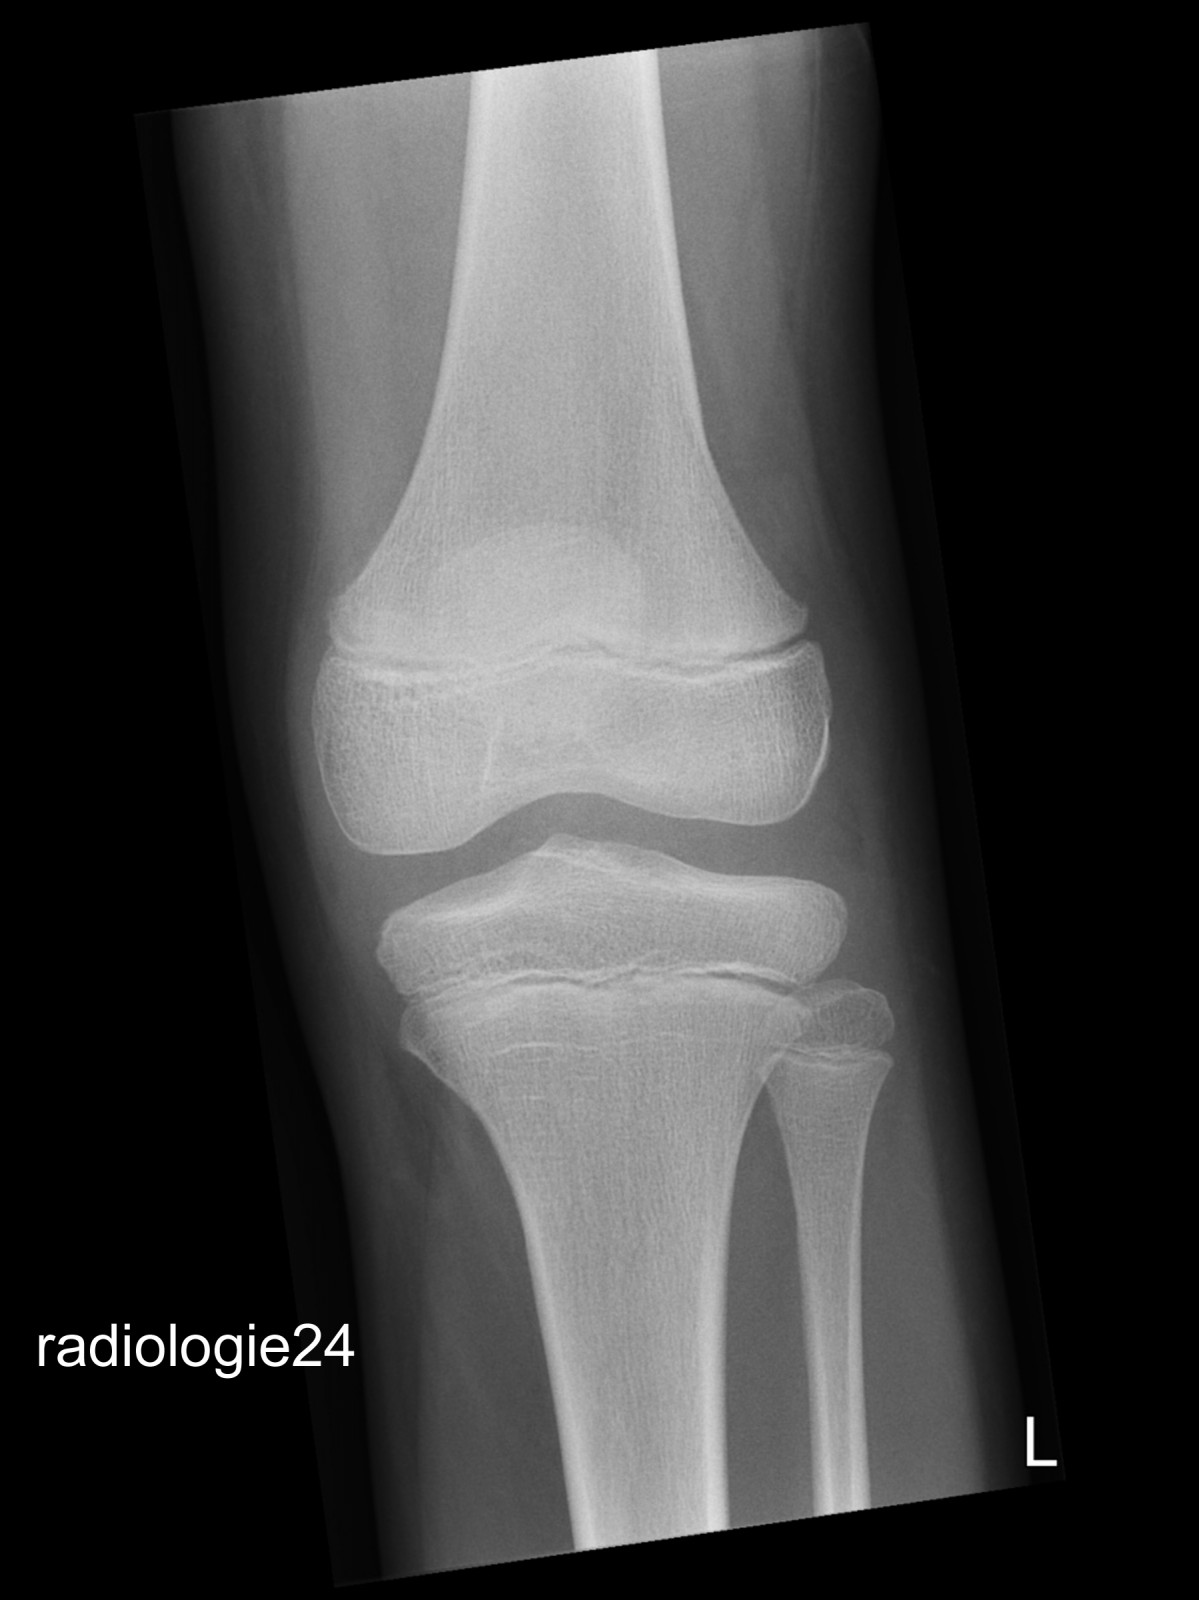

Röntgenfall des Monats März 2018 mit Auflösung

10 jähriger Patient Z.n.Sturz. Schmerzen im Bereich des Kniegelenks Ihre Diagnose?